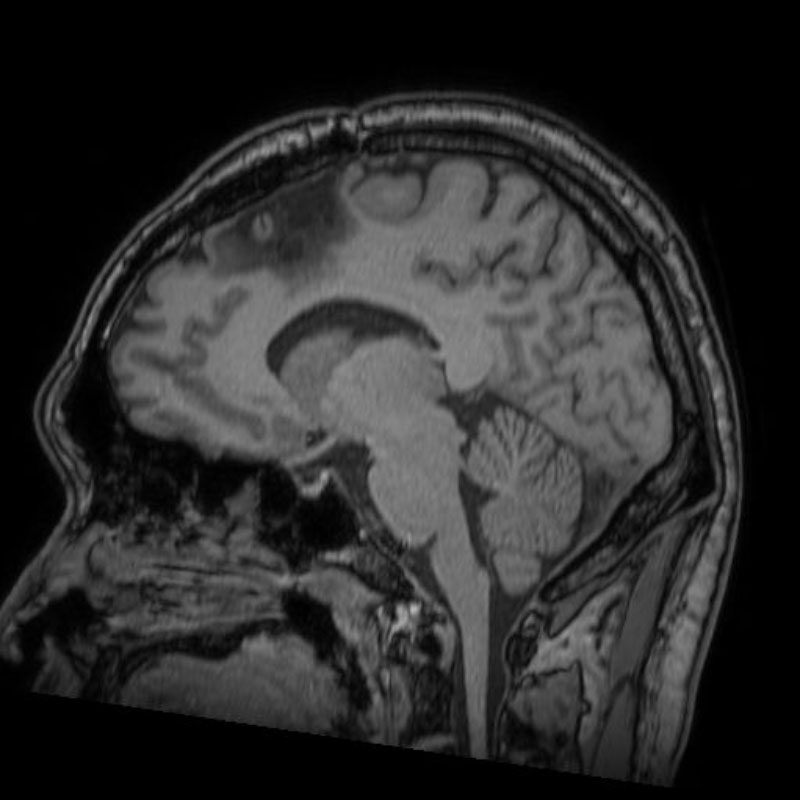

617

'25年3月

80代

大脳悪性腫瘍

No.’25_19 手術前1

No.’25_19 手術前2